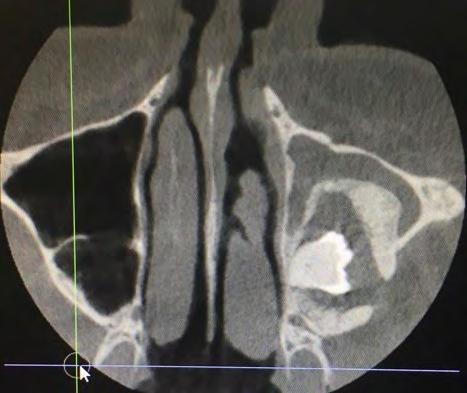

28 An Osteoma Embedding an Ectopic Wisdom Tooth within the Maxillary Sinus A Rare

Kayvan Fathimani, D.D.S., FACS, FRCD(C), FIBCSOMS

Unerupted third molar within maxillary sinus coexisting with maxillary sinus osteoma is extremely rare pathologic finding. Author describes treating patient who presented with this anomaly.

Occurrence